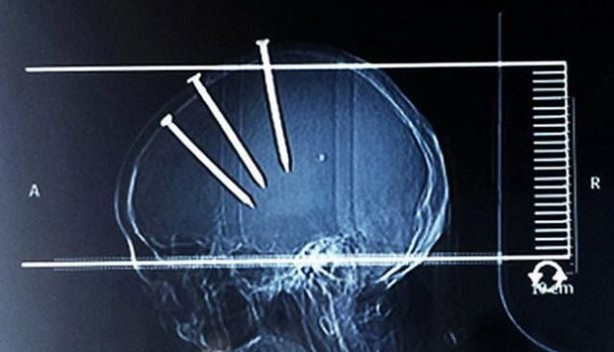

Çinli adam, hastaneye getirildiğinde bu görüntüsü ile herkesi şaşırttı...

Çivilerin başları açıkça dışarıdan bile görünürken doktorlar Çinli adamın röntgenini çekti ve 3 koca çivi ile karşılaştı...

Hemen ameliyata alınan adamın başındaki çiviler teker teker çıkarıldı...

Yapılan araştırmada Çinli adamın evini tamir ederken çivi tabancası ile yaralandığı ortaya çıktı...